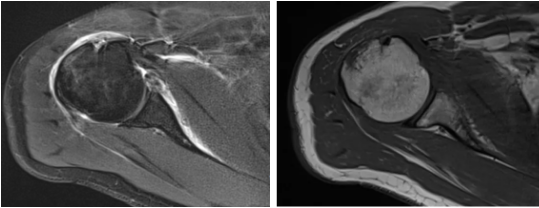

病例1

病史摘要:男性,44歲,跌傷致右肩關(guān)節(jié)疼痛數(shù)天,活動(dòng)不利。

MR圖示:右側(cè)肱骨后外上方局部骨皮質(zhì)塌陷,并鄰近皮質(zhì)下斑片狀壓脂高信號(hào)影(箭頭);前盂唇撕脫,前方見(jiàn)低信號(hào)游離骨片影(三角形)。